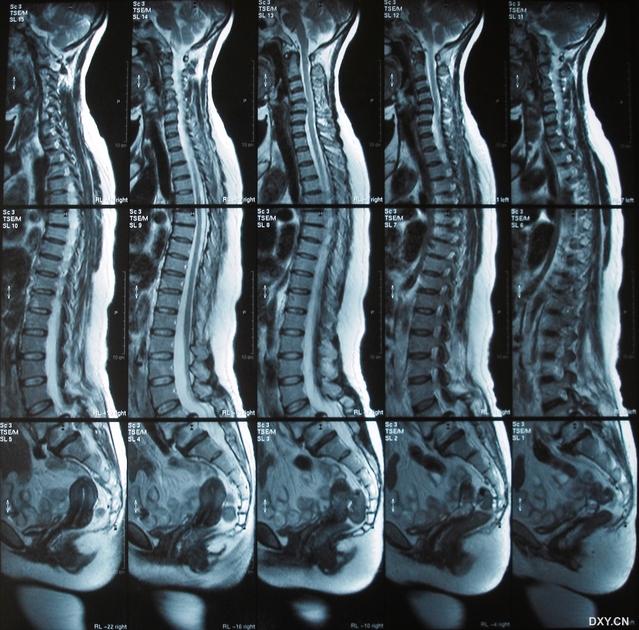

临床视点骨二科成功开展腰椎双侧峡部裂植骨修复手术

年轻人的发育不良性腰椎滑脱峡部裂应当引起重视

腰椎峡部裂1例

多节段腰椎峡部裂伴滑脱需要手术吗

腰椎峡部裂

腰5椎体峡部裂

mis tlif治疗双侧峡部裂,腰椎滑脱症并椎管狭窄症

ct看椎弓根峡部裂

有严重临床症状,无滑脱的腰椎峡部裂的外科治疗方法 - 好大夫在线

什么是腰椎峡部裂

经脊柱内镜下融合术治疗Ⅲ度腰椎滑脱并峡部裂

保留后方张力带结构治疗腰椎Ⅱ度峡部裂滑脱症

典型病例:腰椎峡部裂

病例讨论:腰4椎体双侧峡部裂并2度滑脱 [病例帖]

朱根营 男 31 腰5椎体峡部裂